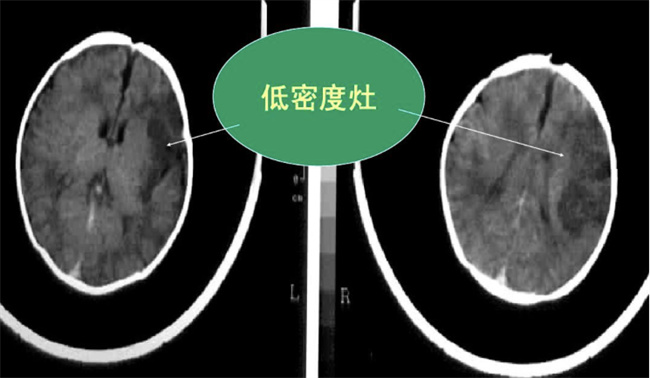

什么是缺氧血性脑病:

缺氧缺血性脑病是一种脑损伤疾病,新生婴儿在获得这种疾病后,一般医生会根据检测来分为轻症中症以及重症,在出现轻症情况下,治愈的概率会比较高,而出现中度或者是重度在治愈上会比较难,一般还会出现脑瘫,甚至是癫痫等症状。 出现缺氧血性脑病原因: